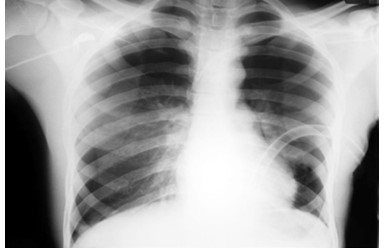

Spontaneous pneumothorax is a common clinical condition in respiratory medicine, typically managed through either conservative measures or pleural drainage. One of the recognized complications following drainage is re-expansion pulmonary edema (REPE), which is usually mild and self-limiting. However, in rare instances, REPE can manifest severely. This report describes a case of unilateral severe REPE that developed shortly after pleural drainage for a spontaneous pneumothorax, complicated by extensive pulmonary plasma leakage. The patient experienced a sudden and critical decline in both respiratory and circulatory status. Emergency management included prone and head-down positioning to optimize ventilationperfusion matching, aggressive fluid resuscitation, and initiation of mechanical ventilation. This clinical course highlights the potential for REPE to progress rapidly to life-threatening respiratory and hemodynamic failure. Clinicians should maintain a high index of suspicion for severe pulmonary re-expansion edema in patients who deteriorate shortly after seemingly successful pleural decompression. Early recognition and supportive interventions are vital for improving outcomes in such critical presentations. In this case report, we discuss such a challenging case, its management and further course we learnt to support our readers.